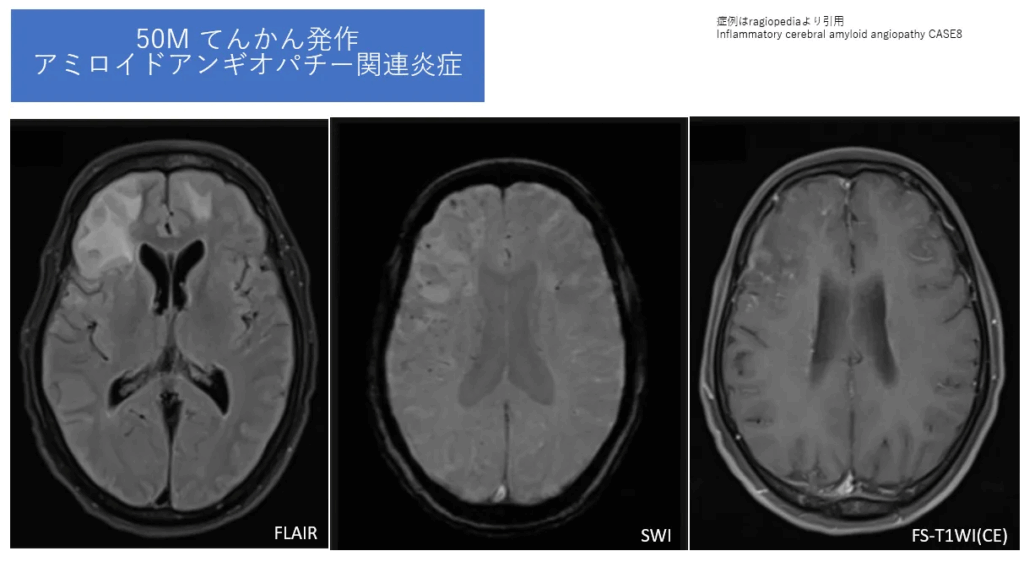

【症例】

50歳男性、てんかん発作で来院。急速な認知機能低下も認める。

まずFLAIR画像を見てください。右の前頭葉を中心に、多くは非対称性で広範な白質浮腫(高信号)が広がっていますね。この所見だけでは、脳腫瘍や感染症など、鑑別診断は非常に多いです。

しかし、ここでCAA-riの可能性を考え、シーケンスを追加します。そこで撮像されたのがSWIです。 するとどうでしょう。浮腫を呈している領域の皮質・皮質下に、背景に隠れていた多数の微小出血が明瞭に描出されました。

この瞬間、診断は大きくCAA-riに傾きます。FLAIRでの浮腫所見に加え、SWIで背景にあるCAAの所見(多発微小出血)を確認することが、CAA-ri診断の決定打となるのです。その他、症例によっては造影剤を投与すると、脳の表面を覆う軟膜が増強される(造影効果を示す)こともあります。